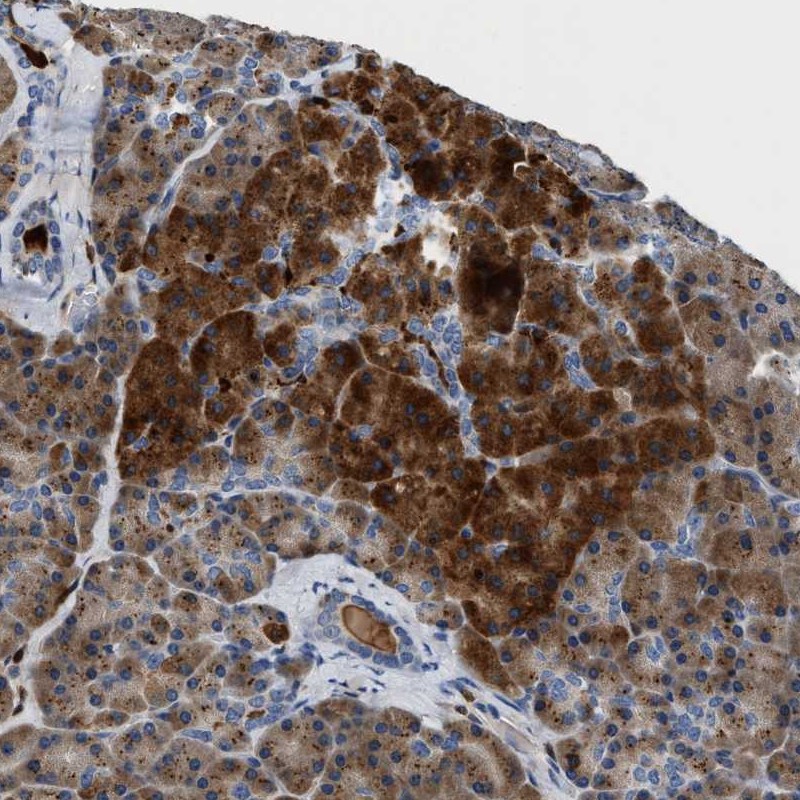

Immunohistochemical staining of human pancreas shows strong cytoplasmic positivity in exocrine glandular cells.